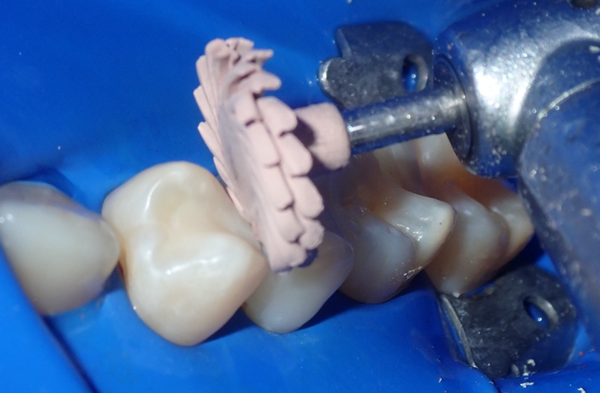

A 38-year-old patient presented with recurrent decay on the distal of tooth #14 and the mesial of tooth #15 (Fig. 1). Both lesions were moderately sized and required replacement of old composite restorations. The treatment plan included direct composite restorations using a total-etch adhesive protocol.

FIG. 1

Initial examination reveals adjacent Class II

carious lesions requiring restoration.